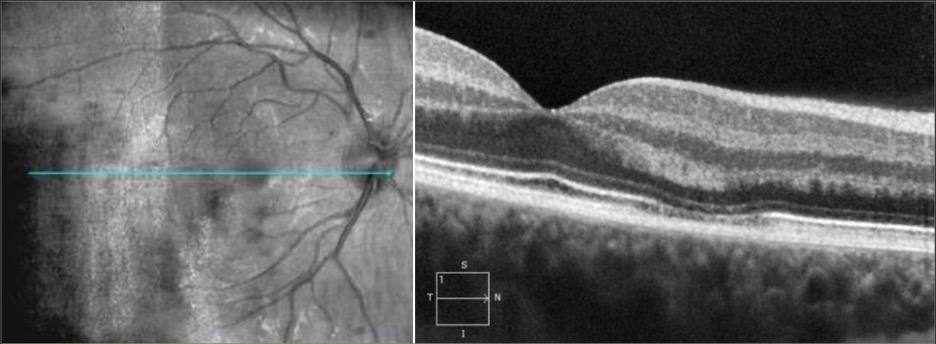

Оптична когерентна томографія (ОКТ): Зовнішній ядерний шар

Зовнішній ядерний шар (ONL – outer nuclear layer) - критично важливий компонент сітківки ока, що складається з тіл фоторецепторних клітин.